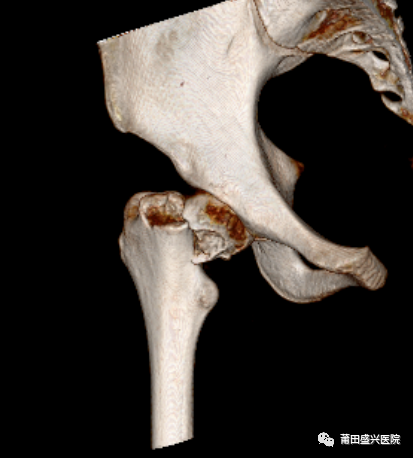

病例分享:患者林某,女,14歲,外傷致右髖疼痛活動(dòng)受限入住莆田盛興醫(yī)院骨科。經(jīng)檢查診斷為“右股骨頸骨折”。

經(jīng)盛興醫(yī)院骨科團(tuán)隊(duì)綜合評(píng)估后,決定為患者實(shí)施“右股骨頸骨折微創(chuàng)復(fù)位FNS內(nèi)固定術(shù)”治療。在林國(guó)兵院長(zhǎng)、黃益平主任醫(yī)師及骨科團(tuán)隊(duì)的共同努力下,手術(shù)于2022年1月18日在麻醉科及手術(shù)室醫(yī)護(hù)的全力配合下順利完成,術(shù)后透視復(fù)位佳,內(nèi)固定位置良好?;颊咝g(shù)后1周康復(fù)出院。